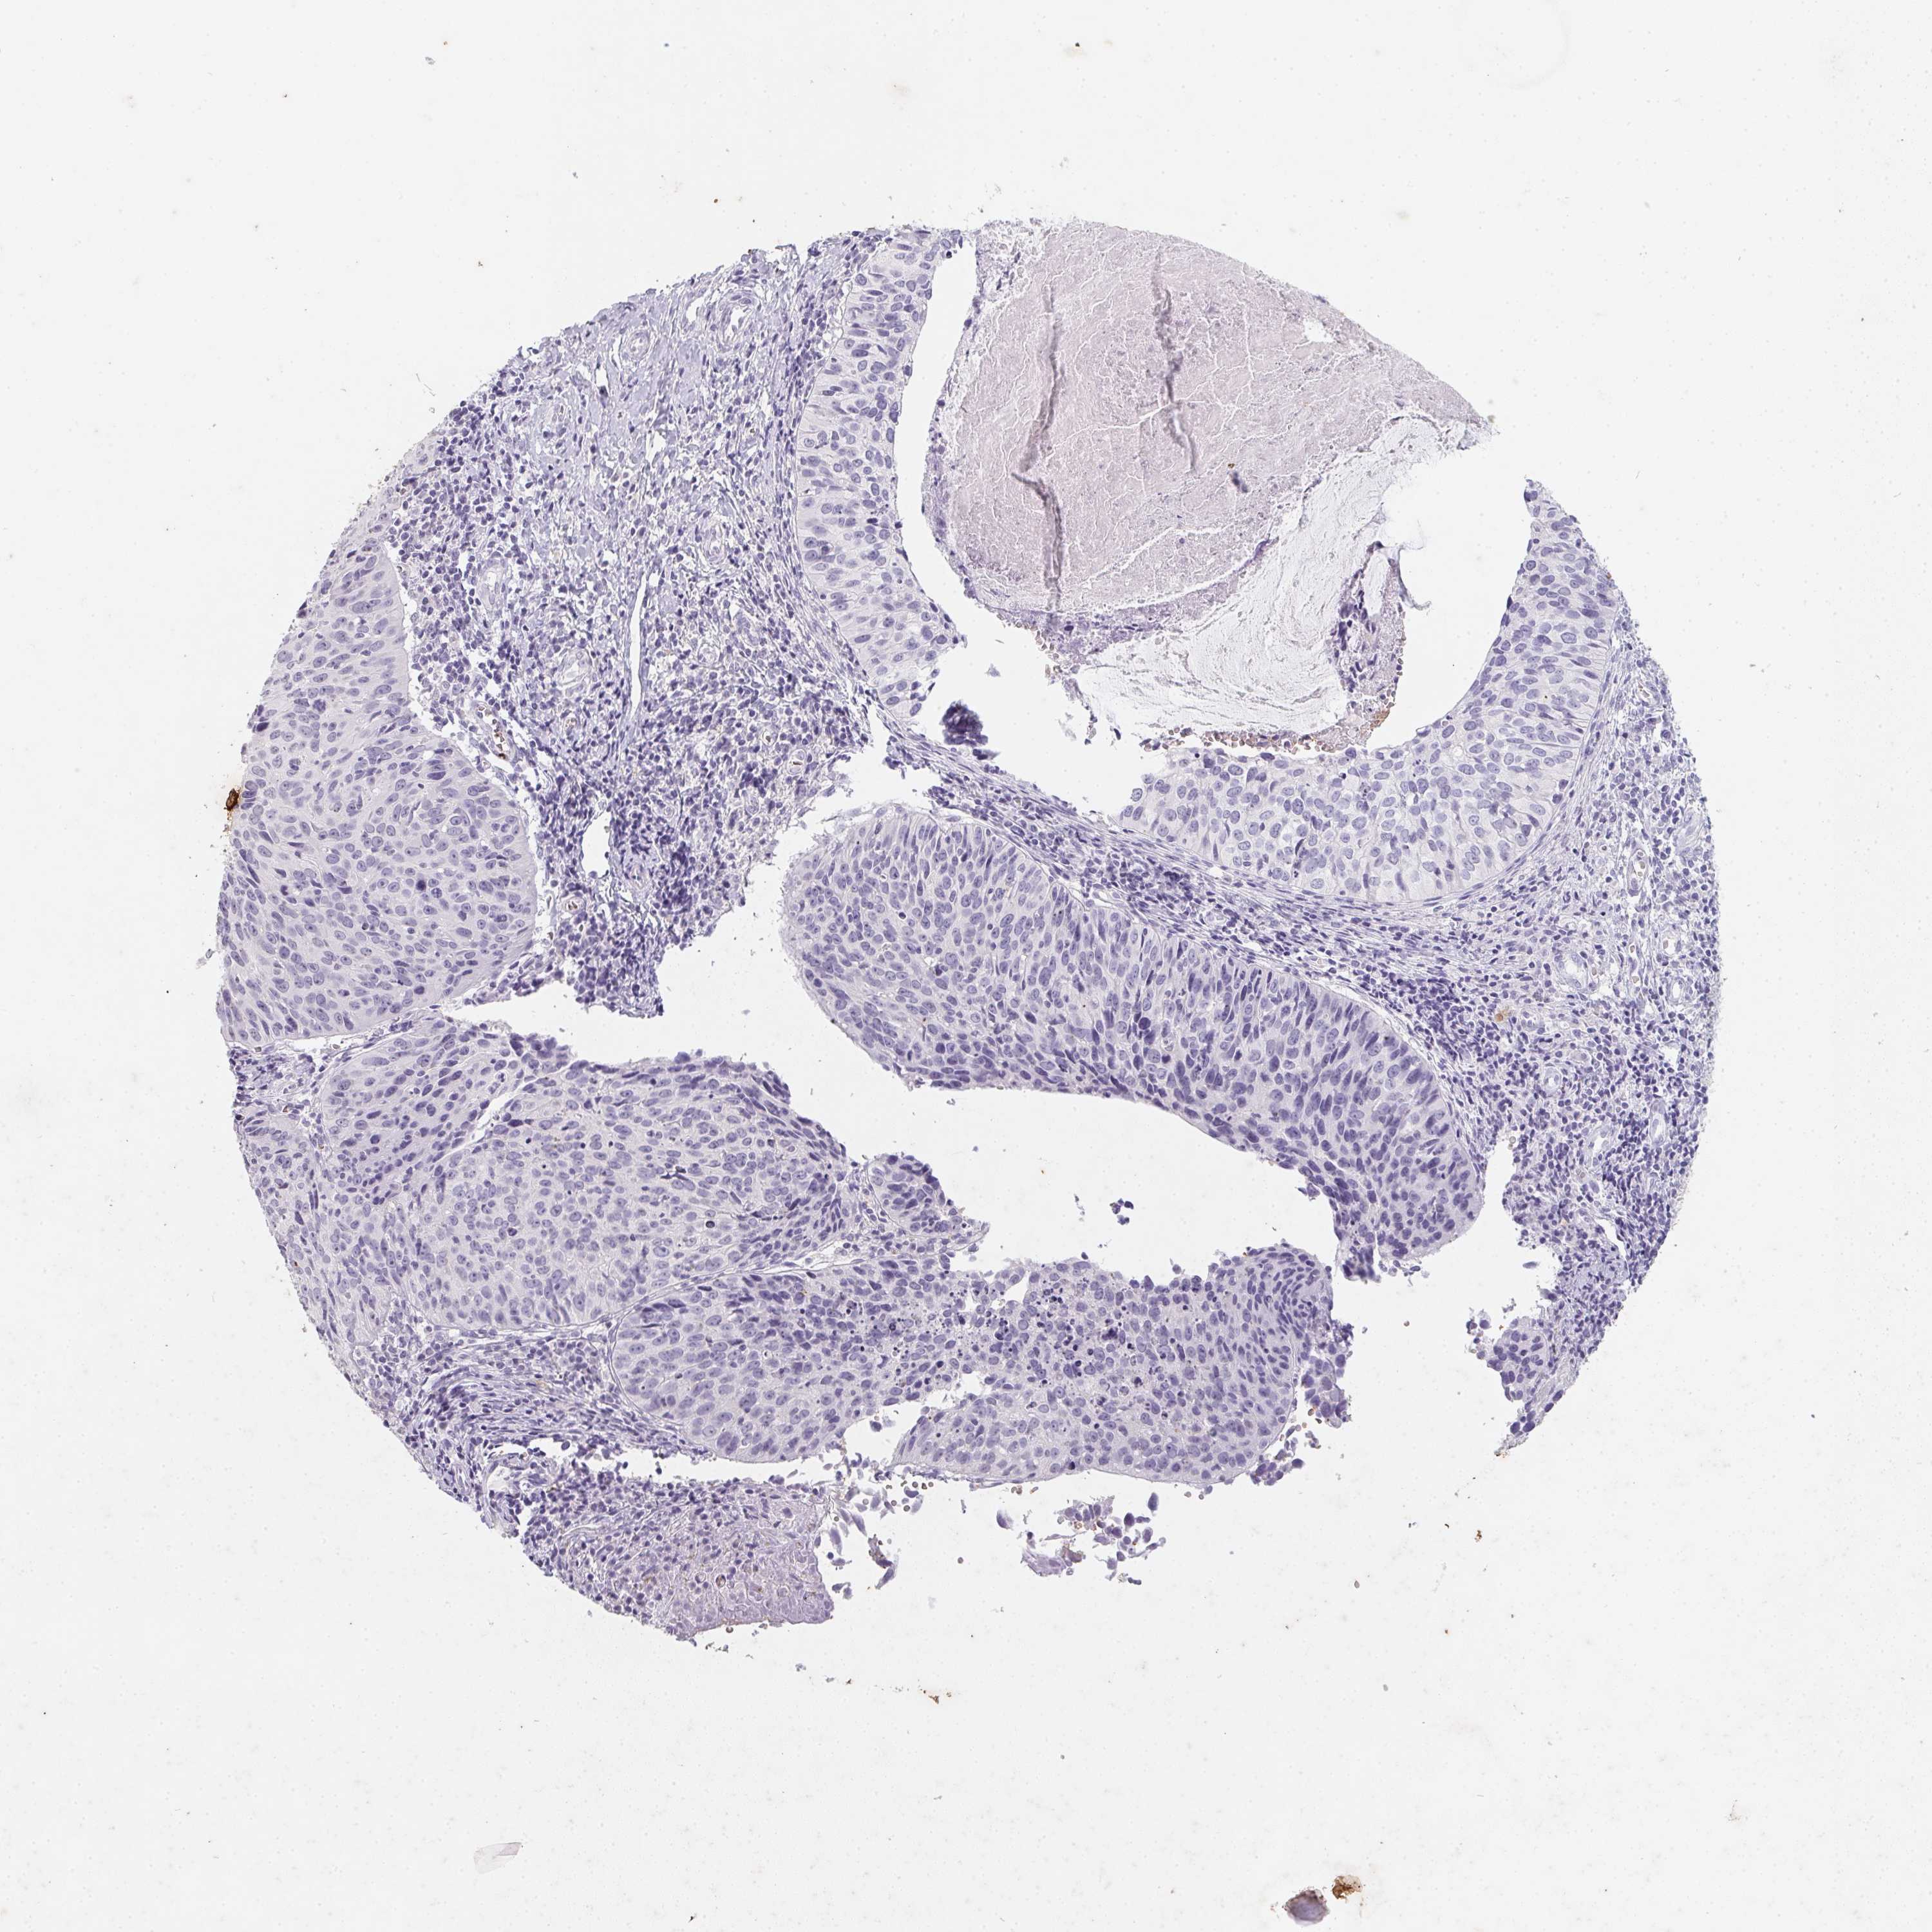

CERVICAL CANCER - Protein expressioni

A mouse-over function shows sample information and annotation data. Click on an image to view it in a full screen mode. Samples can be filtered based on level of antibody staining by selecting one or several of the following categories: high, medium, low and not detected. The assay and annotation is described here.

Note that samples used for immunohistochemistry by the Human Protein Atlas do not correspond to samples in the TCGA dataset.

Antibody stainingi

Antibody staining in the annotated cell types in the current human tissue is reported as not detected, low, medium, or high, based on conventional immunohistochemistry profiling in selected tissues. This score is based on the combination of the staining intensity and fraction of stained cells.

Each image is clickable and will lead to virtual microscopy that enables deeper exploration of all samples and also displays staining intensity scores, fraction scores and subcellular localization as well as patient and tissue information for each sample.

Antibody HPA063967

Staining

High

Medium

Low

Not detected

Intensity

Strong

Moderate

Weak

Negative

Quantity

>75%

75%-25%

<25%

None

Location

Nuclear

Cytoplasmic/membranous

Cytoplasmic/membranous,nuclear

Squamous cell carcinoma, NOS

Adenocarcinoma, NOS